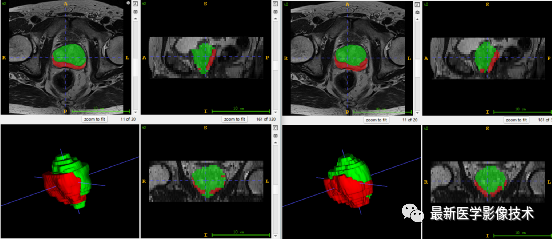

5、验证集分割结果

左边是金标准结果,右边是网络预测结果。